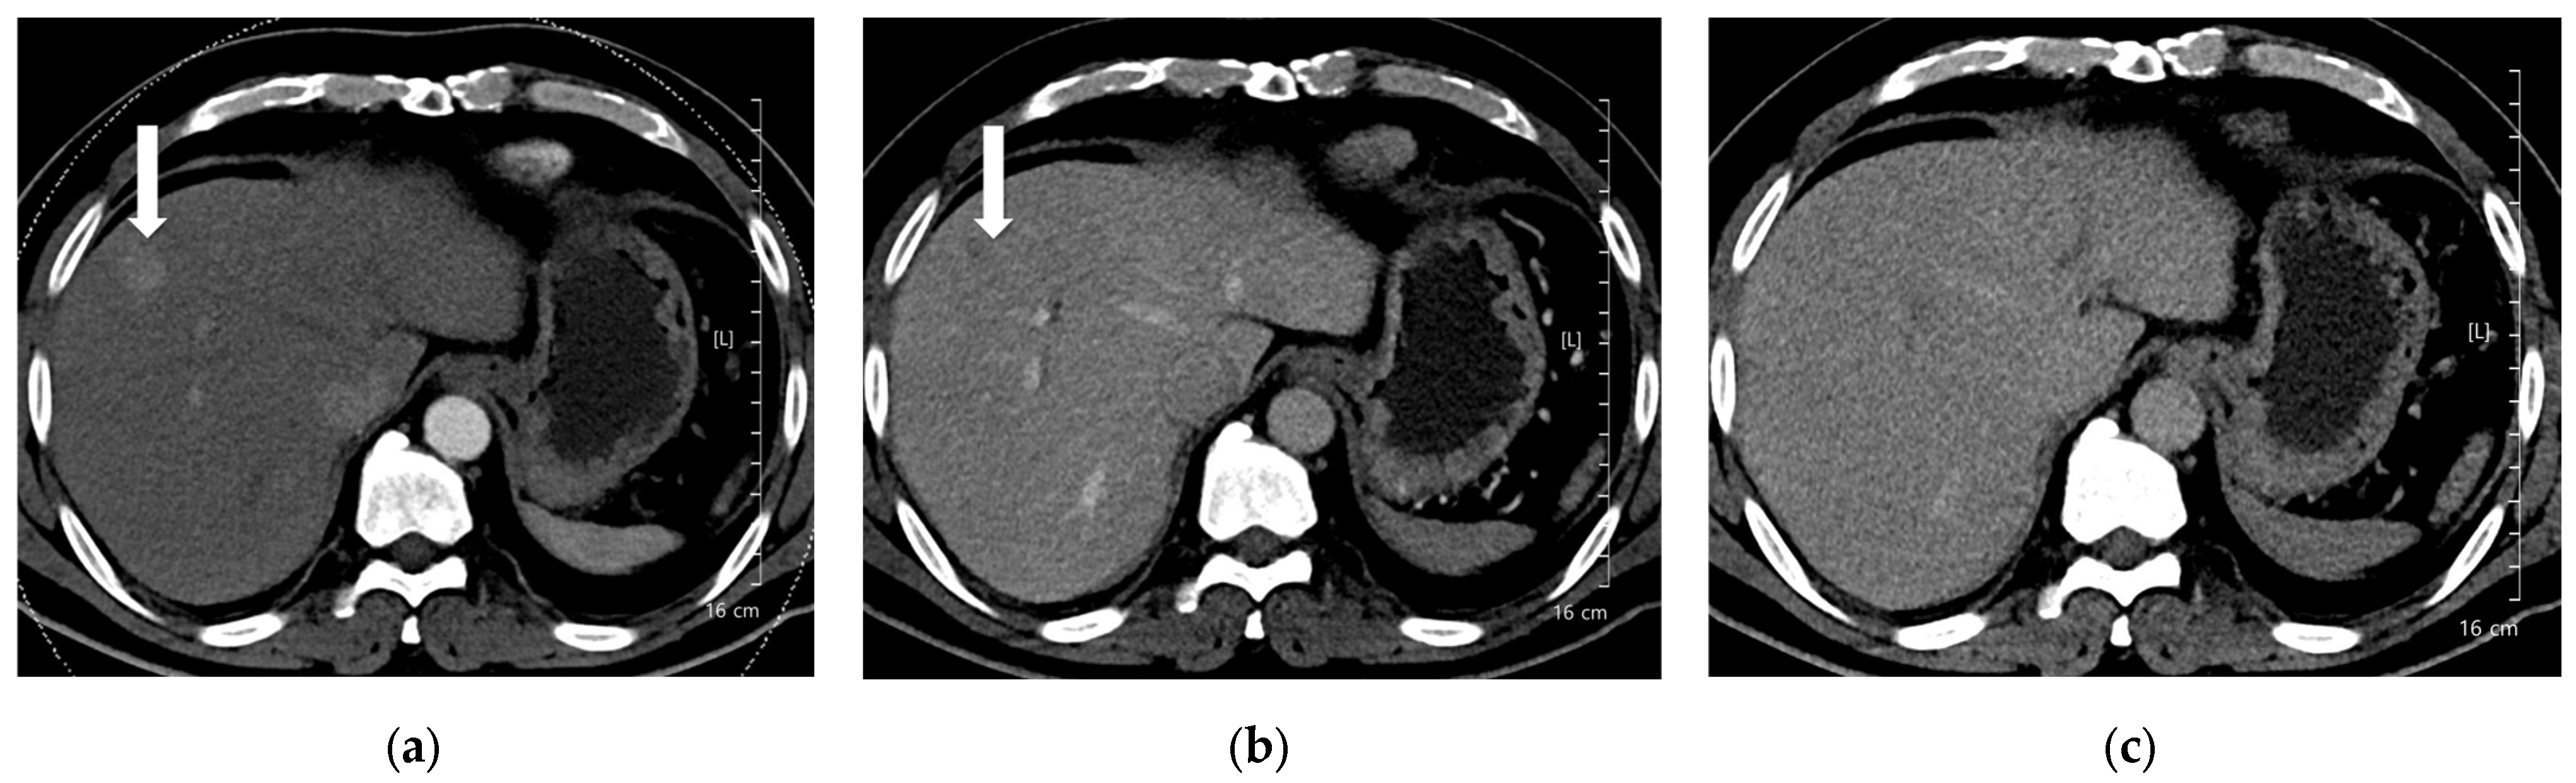

A total of 168 focal liver lesions were identified in 93 participants (80 lesions in the high-concentration iodine group [n = 47] and 88 lesions in the low-concentration iodine group [n = 46]). Lesions comprised HCCs (n = 80), adenocarcinomas (n = 14), dysplastic nodules (n = 15), hemangiomas (n = 33), and regenerative nodules (n = 3). Lesion size was equivalent between the high- and low-concentration iodine groups (14.36 ± 14.72 mm versus 17.50 ± 12.27 mm, p = 0.134). Per-lesion detectability showed no significant difference between the groups (0.862 versus 0.909, p = 0.18; Table 6). Among detected lesions, the mean conspicuity score was significantly higher in the LCIC group than in the HCIC group (4.41 versus 4.07, p = 0.002) (Figure 3, Figure 4, Figure 5 and Figure 6).

Figure 6. A 91-year-old woman with hepatocellular carcinoma (HCC). CT was performed using low-concentration iodine contrast material (total iodine dose, 518.4 mg I/kg). Overall image quality in the arterial and portal phases was acceptable. (a) An 8-mm enhancing nodule (arrow) is visible on the arterial phase at 100 kVp; (b,c) The nodule shows washout on the portal and delayed phases (arrows). Both reviewers classified the lesion as hepatocellular carcinoma.